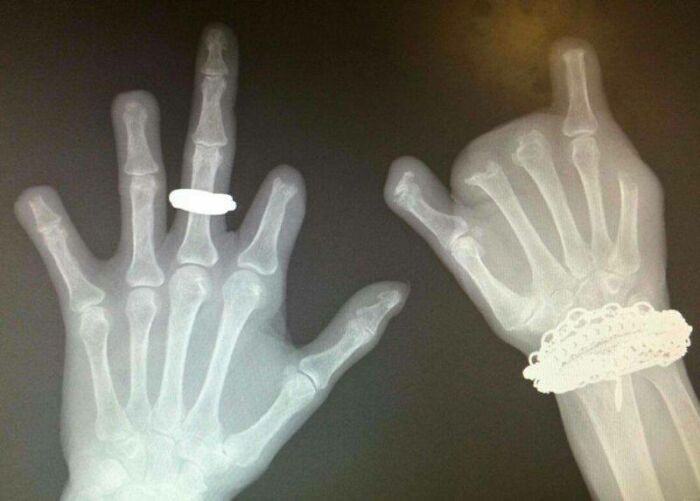

La radiografía dental de mi hijo de 6 años